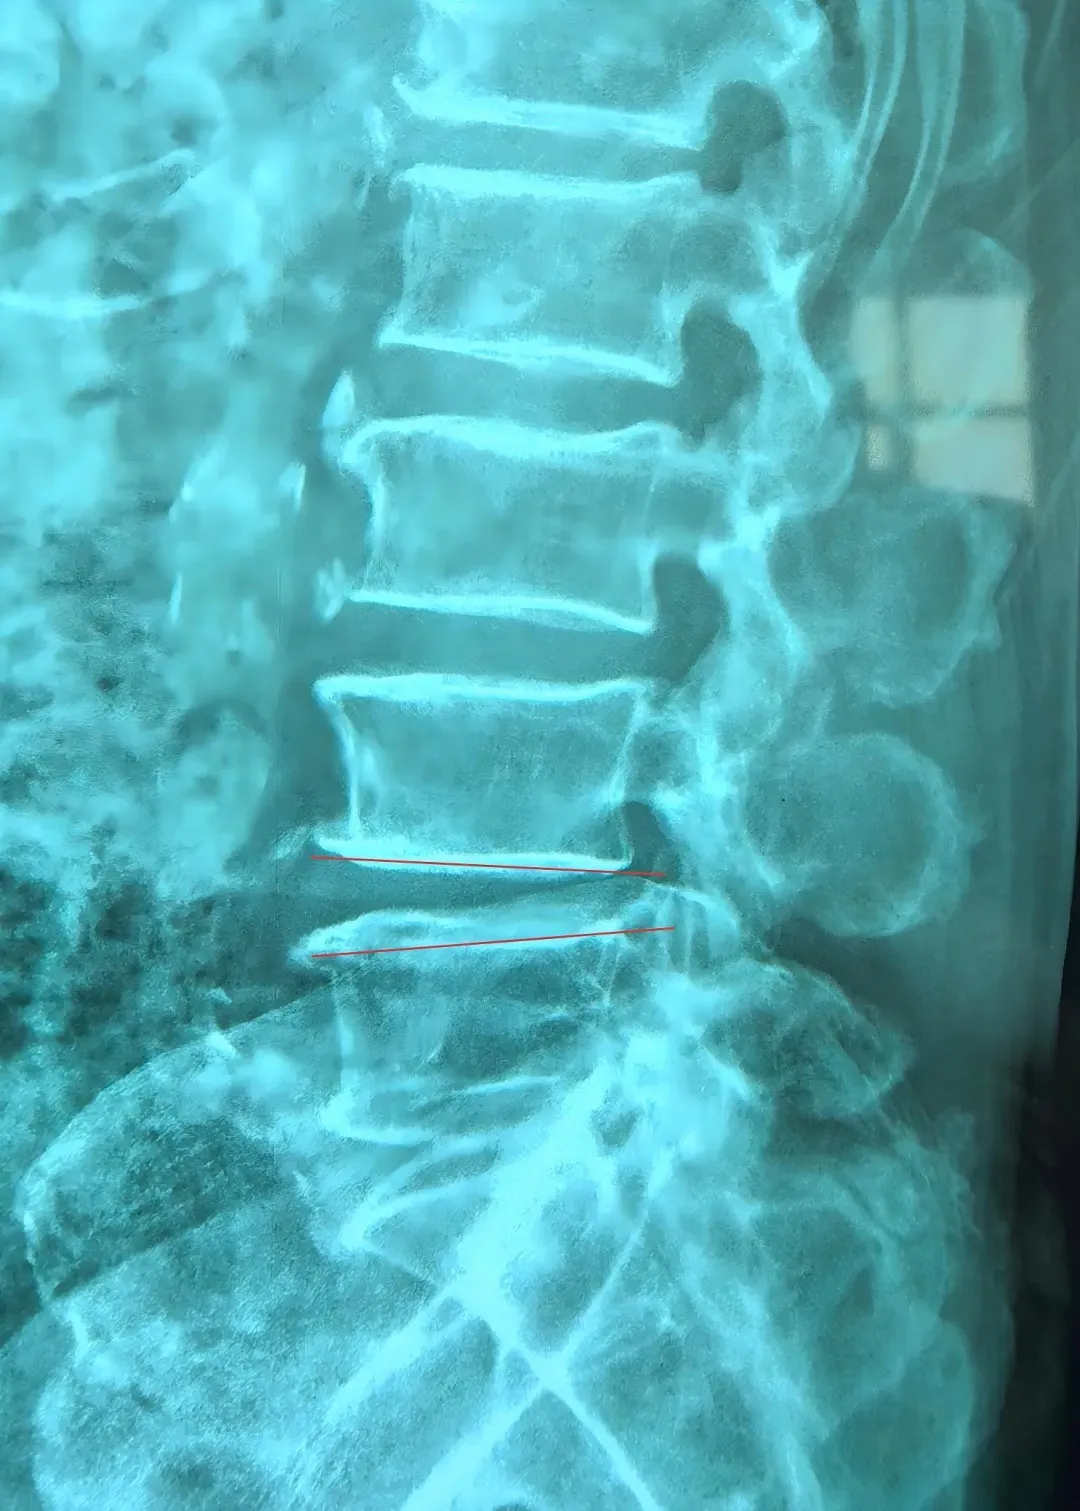

IMG_256 李龍主任詳細閱讀影像學資料并再次對患者進行全面評估,明確了病因:腰4-5節(jié)段重度椎管狹窄合并腰椎失穩(wěn)。這正是導致患者下肢劇烈疼痛和行走困難的“罪魁禍首”。李主任向患者及家屬詳細解釋了病情:椎管狹窄使得神經受壓,腰椎失穩(wěn)則加劇了這種壓迫和炎癥反應,保守治療在此階段難以解決根本問題。他建議施行微創(chuàng)減壓融合術,徹底解除神經壓迫,重建腰椎穩(wěn)定。 IMG_258 當聽到可以通過手術進行“減壓”時,被病痛折磨多年的老人仿佛看到了曙光,如同抓住了“救命稻草”。在充分理解手術必要性與微創(chuàng)技術的優(yōu)勢后,患者及家人消除了對高齡手術的恐懼,果斷接受了李龍主任提出的手術方案。經過周密的術前準備,手術如期進行。李龍主任團隊憑借精湛的微創(chuàng)技術,成功為患者實施了腰4-5微創(chuàng)減壓融合術。手術過程順利,術中出血極少。術后,困擾患者多年的腿疼癥狀得到了很大緩解。令人欣喜的是,在術后第三天,老人便在醫(yī)護人員指導下,佩戴支具下地行走。邁步的那一刻,患者及其家屬的臉上露出了久違的笑容。對梁振斌主任的精準初判、李龍主任的高超技術以及整個醫(yī)療團隊的精心照護表示了無盡的感激。 IMG_260 本例高齡患者的成功救治,充分體現(xiàn)了精準診斷、多學科協(xié)作以及現(xiàn)代脊柱微創(chuàng)技術的巨大優(yōu)勢。李龍主任提醒,如果腰腿痛長期保守治療無效,特別是疼痛加重、行走越來越困難的患者,應盡早到正規(guī)醫(yī)院就診,由醫(yī)生評估是否需要手術。微創(chuàng)手術技術成熟,可以為許多高齡、高風險患者提供安全有效的治療,避免延誤病情導致神經不可逆的損傷。(李 ? 勇)